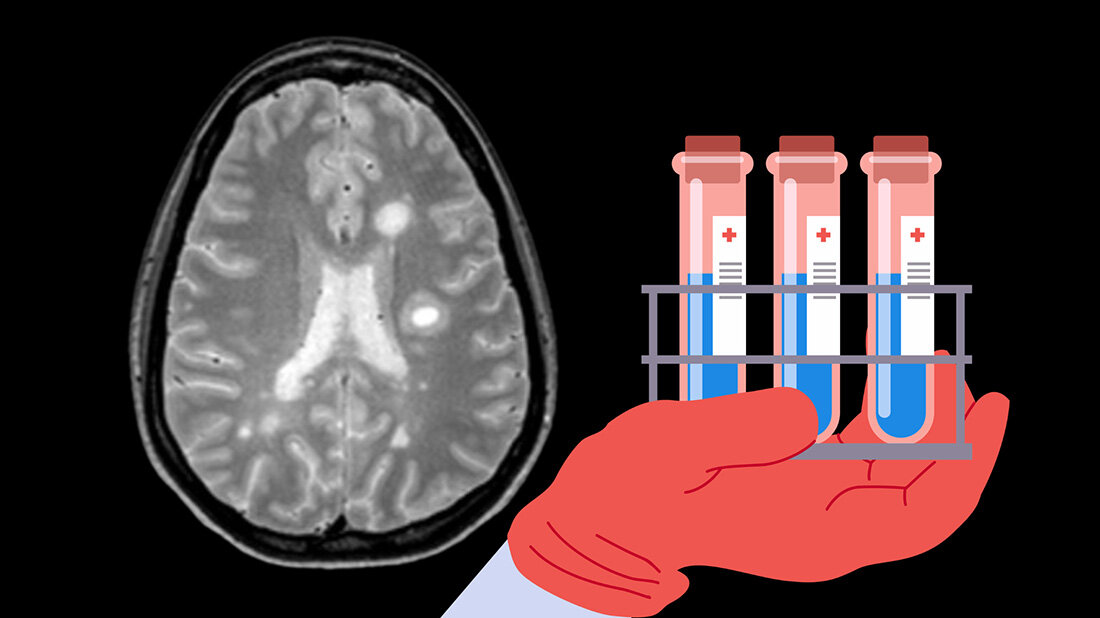

Unerklärliche neurologische Symptome stellen für Patientinnen und Patienten unangenehme Ungewissheit über den eigenen gesundheitlichen Zustand dar und stellen Ärztinnen und Ärzte vor eine Herausforderung. Denn trotz moderner Bildgebung fehlen verlässliche Biomarker, die genutzt werden können, wenn die Bildgebung keine sichere Diagnosestellung ermöglicht. Bisher basiert die Diagnose von Multipler Sklerose (MS) auf einer Mischung aus MRT und Analyse des Liquors. In 10 Prozent der Fälle fehlen die typischen MS-Marker, die oligoklonalen ANtiköreprbande, und es ist keine sichere Diagnose möglich. Hier könnten in Zukunft neu entdeckte Biomarker greifen.

Die Forschenden konnten eine Gruppe von 22 Proteinen identifizieren, die MS von anderen, ähnlich entzündlichen Erkrankungen unterscheiden. Diese Proteine können MS genauer abgrenzen als bisher in der Praxis verwendete Parameter im Liquor. Außerdem entdeckten sie einen Hinweis auf den Krankheitsverlauf. Während manche Patientinnen und Patienten jahrelang stabil bleiben, entwickeln andere schneller Beeinträchtigungen oder wechseln früh vom schubförmigen Verlauf in den progressiven Verlauf. Die Analyse der Proben zeigte hier den Zusammenhang des Proteoms im Liquor zum Zeitpunkt der Diagnose mit dem Grad der Beeinträchtigung. Diese Erkenntnisse, sobald sie im klinischen Alltag eingesetzt werden können, führen zu einer präziseren Diagnostik und einer Möglichkeit zur frühzeitigen individuellen Behandlungsstrategie. Auch die Übertragung der neuen Proteomik-Methode auf weitere neurologische Erkrankungen ist möglich, kommentiert Prof. Mann. So würde die Art und Weise revolutioniert werden, wie nach Biomarkern gesucht würde.